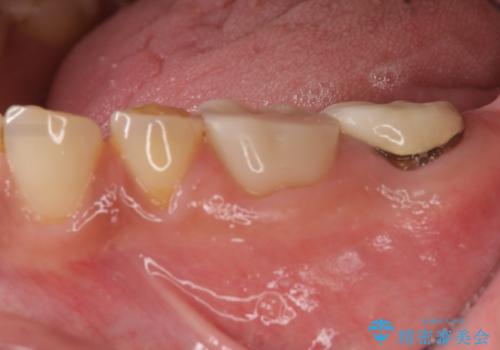

歯周外科で達成する、安定したクラウン周囲の歯肉環境

放置された虫歯 小矯正+歯周外科による保存処置